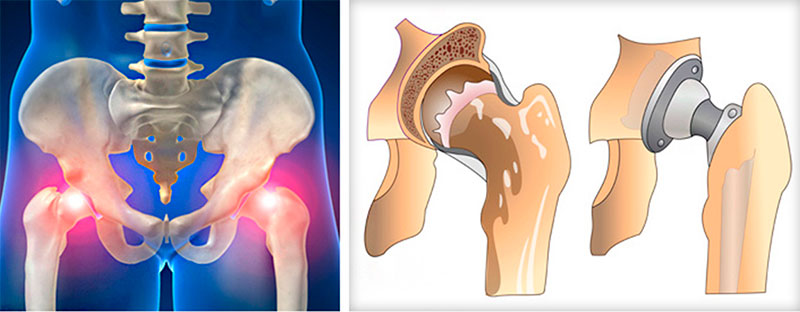

Замена таз сустава

Замена таз сустава 113 фотографий